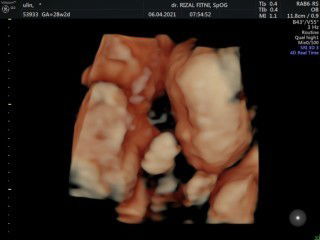

Bayi kembar,yang satu meninggal dalam rahim

Hallo bunda,pengen sharing nih,usia kandunganku saat ini memasuki 7 bulan.dan aku hamil kembar..kemarin setelah usg ternyata salah satu janin tidak berkembang dan meninggal..dikhawatirkan pembusukan janin yang meninggal bisa meracuni si ibu dan mempengaruhi kembarannya..mungkin para bunda ada yang pernah mengalami hal yang sama..#bantusharing #ingintahu